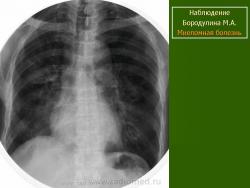

Миеломная болезнь

click to enlargeclick to enlargeclick to enlargeclick to enlarge